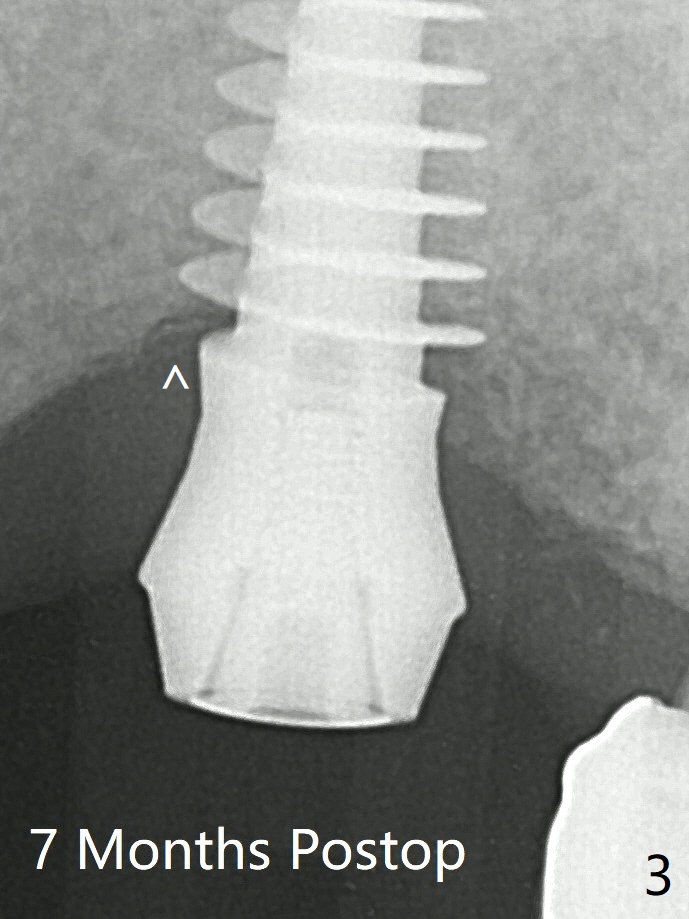

Probably due to underprep, the mesial crestal bone appears to have been resorbed 7 months postop (Fig.3 ^, as compared to Fig.1 *). The temp bond cemented crown is off 8 months post cementation (Fig.6). The bone density increases especially mesial.